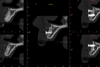

Indication de la greffe |

Indication de la greffe

Sect 12, 5 mois plus tard